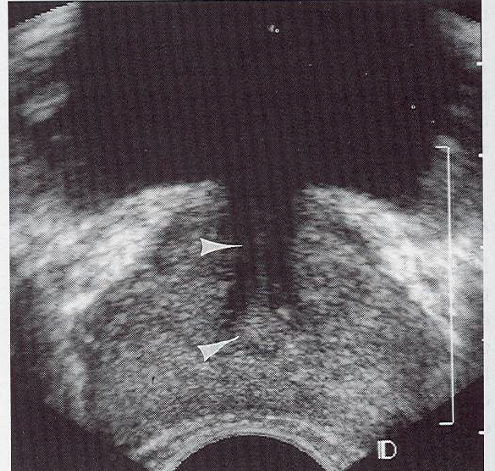

what is this showing?

seminal vesicle